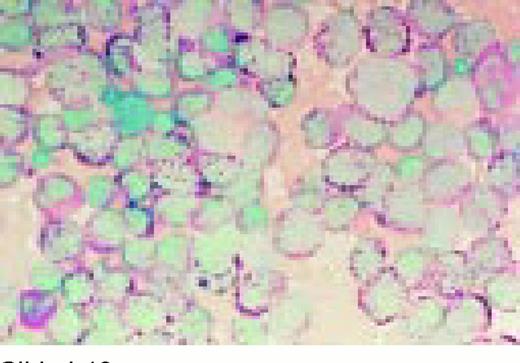

Slide L35

Burkitt's lymphoma. Composite: bone marrow biopsy (L) and bone marrow aspirate (R). Giemsa stained. This 19-year-old male presented with a submandibular tumor in 1997. A biopsy revealed non-Hodgkin's lymphoma, Burkitt's type, according to the REAL classification. Staging revealed stage I disease. He was treated with aggressive polychemotherapy for Burkitt's lymphoma and an allogeneic bone marrow transplant was planned for March 1998. Two weeks before BMT, the patient complained of back pain, and there was a sharp rise of LDH. A bone marrow smear and biopsy revealed massive infiltration by Burkitt lymphoma blasts. Few tumor cells were seen in the blood smear. The slide (R) shows typical Burkitt's lymphoma with vacuolated cytoplasm (ALL-L3 blasts according to the FAB classification). The bone marrow biopsy (L) also shows the typical, leukemia type, interstitial infiltration, leaving the fat cells intact.FIG35